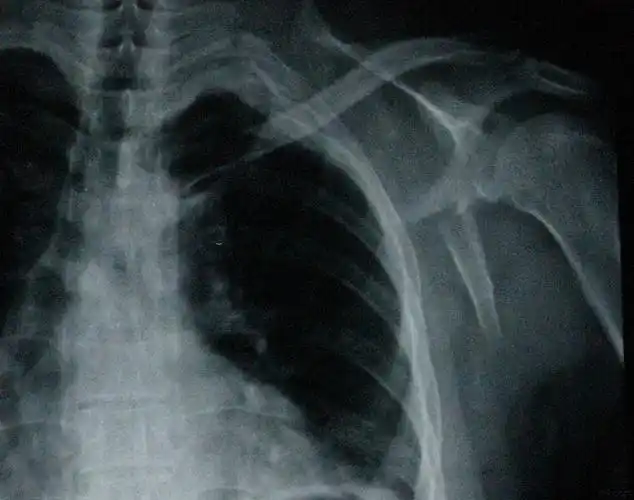

中西医结合治疗右肩胛骨粉碎骨折气滞血瘀

肩胛骨骨折

一例肩胛骨骨折

肩胛骨骨折,求讨论